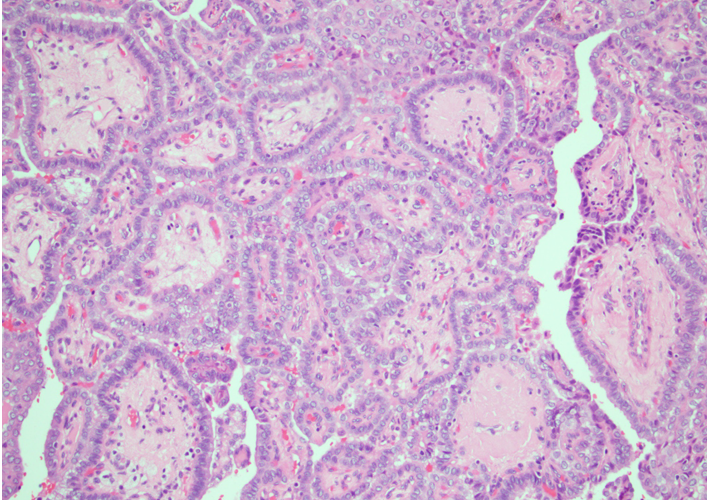

-normal thyroid- lobular architecture

-normal thyroid- cuboidal follicular epithelial cells